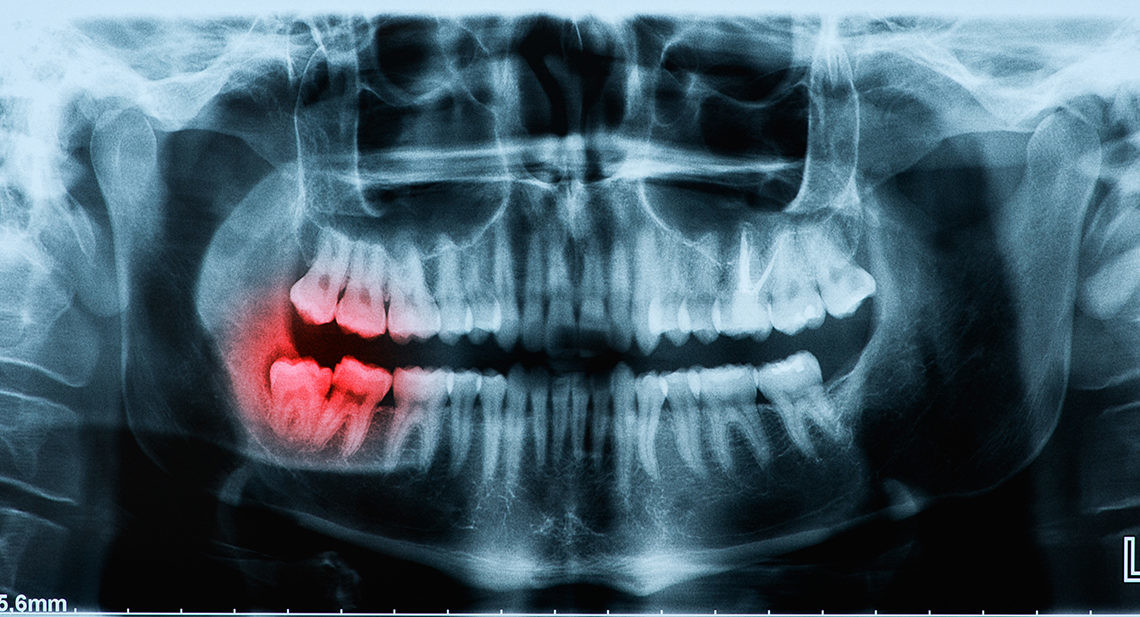

Broken Wisdom Tooth – Is It Considered An Emergency?

Wisdom teeth are usually the last adult teeth to come through and tend to erupt in the later teens or early twenties. Known as the third molars, they do not always come through the gums at all, and if they do, sometimes they may not be straight.

In these cases, there may be an increased risk of infection. Gaps allow debris to gather and bacteria to grow, which raises the risk of gum disease and tooth decay. Some experts recommend the early removal of wisdom teeth to avoid such occurrences, while others believe it is best to leave them alone if possible.

However, one situation where your dentist is very likely to recommend removal is if a wisdom tooth is broken. While it is possible to retain the broken tooth, to avoid further complications, it is best to get the tooth removed completely.

Why Do Wisdom Teeth Break?

As wisdom teeth are the last to come through, there may be limited space in your mouth. As they try to erupt through your gum, another tooth may already be occupying the same spot. Your wisdom tooth may come through at an unnatural angle, or even crack as it forces its way out.

Wisdom teeth may be more likely to break than your other teeth if they have not erupted correctly. You may find it more challenging to use those teeth to chew, and there is a greater chance of decay if it is harder to clean thoroughly around that area.

As with any other tooth, your wisdom teeth are susceptible to blunt force trauma, such as an impact on your jaw, or biting into something hard. If your teeth crack, or fragments of your wisdom tooth break off, this is likely to cause discomfort.

Risks from Having a Broken Wisdom Tooth

Bacteria can thrive in gaps where bits of the tooth broke. A gap in a wisdom tooth is a hospitable environment for an infection and a weak point in the tooth.

Additionally, a broken or cracked wisdom tooth puts the entire tooth’s health at risk. Bacteria can invade the tooth and infect the dental pulp. In those cases, the tooth must either be extracted or given a root canal treatment. In most cases, it’s better just to remove the tooth.